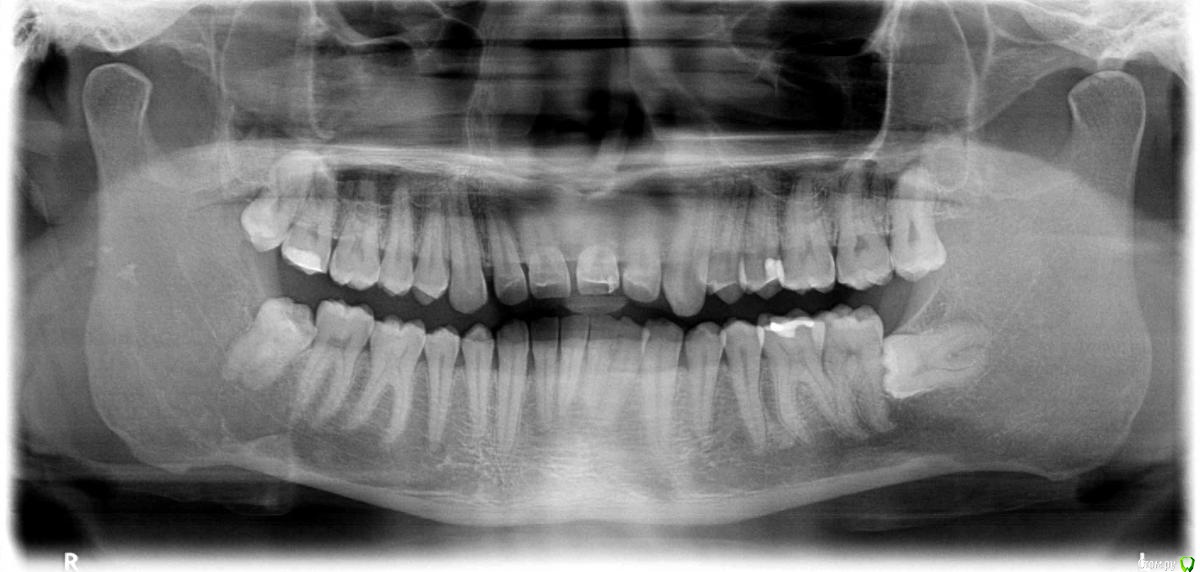

kozloff Опубликовано 15 ноября, 2015 Поделиться Опубликовано 15 ноября, 2015 Да, нужно исключить синусит.А еще можно заподозрить дисфункцию ВНЧС, на вашем снимке (ОПТГ) вызвает опасение расположение суставных головок. Но это может быть дефект снимка.Обязательно сделайте КТ, на одном снимке можно и пазухи рассмотреть, и ВНЧС. Ссылка на комментарий

kozloff Опубликовано 18 ноября, 2015 Поделиться Опубликовано 18 ноября, 2015 Подозреваю пульпит зуба 25И к лору не помешает сходить, есть отек слизистой. Гайморита нет. Ссылка на комментарий

Jurai Опубликовано 22 ноября, 2015 Поделиться Опубликовано 22 ноября, 2015 Есть проблема во фронтальном участке верхней челюсти: общая убыль костной ткани, ячеистая структура кости. смещение зубов так, что корни изогнулись, это значит, что либо резорбция (рассасывание) либо очень длительное уже идет воздействие. Могу подозревать новооборазование в этом участке.Вам нужна консультация челюстно-лицевого хирурга-онколога. 1 Ссылка на комментарий

kozloff Опубликовано 29 ноября, 2015 Поделиться Опубликовано 29 ноября, 2015 Не могут ли подобные симптомы говорить о каком либо бактериальном заражении либо воспалительном процессе? Нет. Рекомендую начать с малого. Обратите внимание на зубы 25, 26. Там возможен кариес/пульпит. Обратитесь на очную консультацию для этого к терапевту-стоматологу. Далее консультация ортодонта. 2 Ссылка на комментарий

janis1 Опубликовано 14 декабря, 2015 Автор Поделиться Опубликовано 14 декабря, 2015 Итак, продолжение моей эпопеи.Удалось попасть к челюстно-лицевому хирургу-онкологу раньше чем было запланировано. После очного осмотра и изучения КТ, профессор выдал заключение, что никаких проблем по его части он не нашел.После этого я был у терапевта, по поводу 25 -26 зубов, ничего кроме зубного камня на 26 зубе (кстати напомню я недавно делал гигиену ) он так-же ничего не нашел.На всякий случай сделали рентген зубов, даже как я понял с двух сторон, вот снимки: Ну и самое главное - проблема осталась, то-есть уже более двух месяцев я живу с болью в районе верхней челюсти...Что делать дальше не знаю...Очень надеюсь на вашу помощь! Ссылка на комментарий